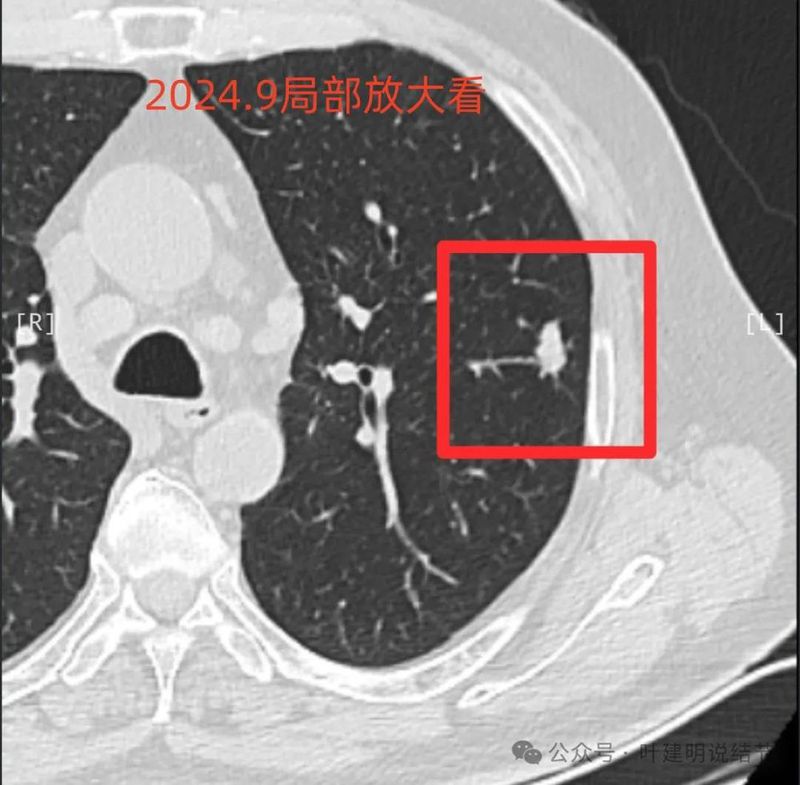

2024年9月24日 病人感冒,咳嗽,入住当地三甲医院,依然按炎症处理,此时左肺上叶段结节14*9mm,右肺上叶5*4mm结节, 引起重视,CT及影像见附件1 ;

2024年9月再增大进展,见血管进入明显,靠血管这侧的边缘较为毛糙。

局部放大病灶表面不平,血管进入,进入的血管有异常增粗,没有见到明显卫星病灶。